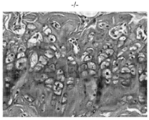

도 3a 및 도 3b는 야생형(도 3a) 및 동형접합체 녹아웃(도 3b) 마우스 유래의 헤마톡실린 및 에오신 염색된 대퇴부 연골의 대표 절편의 광학 현미경 이미지를 보여준다.